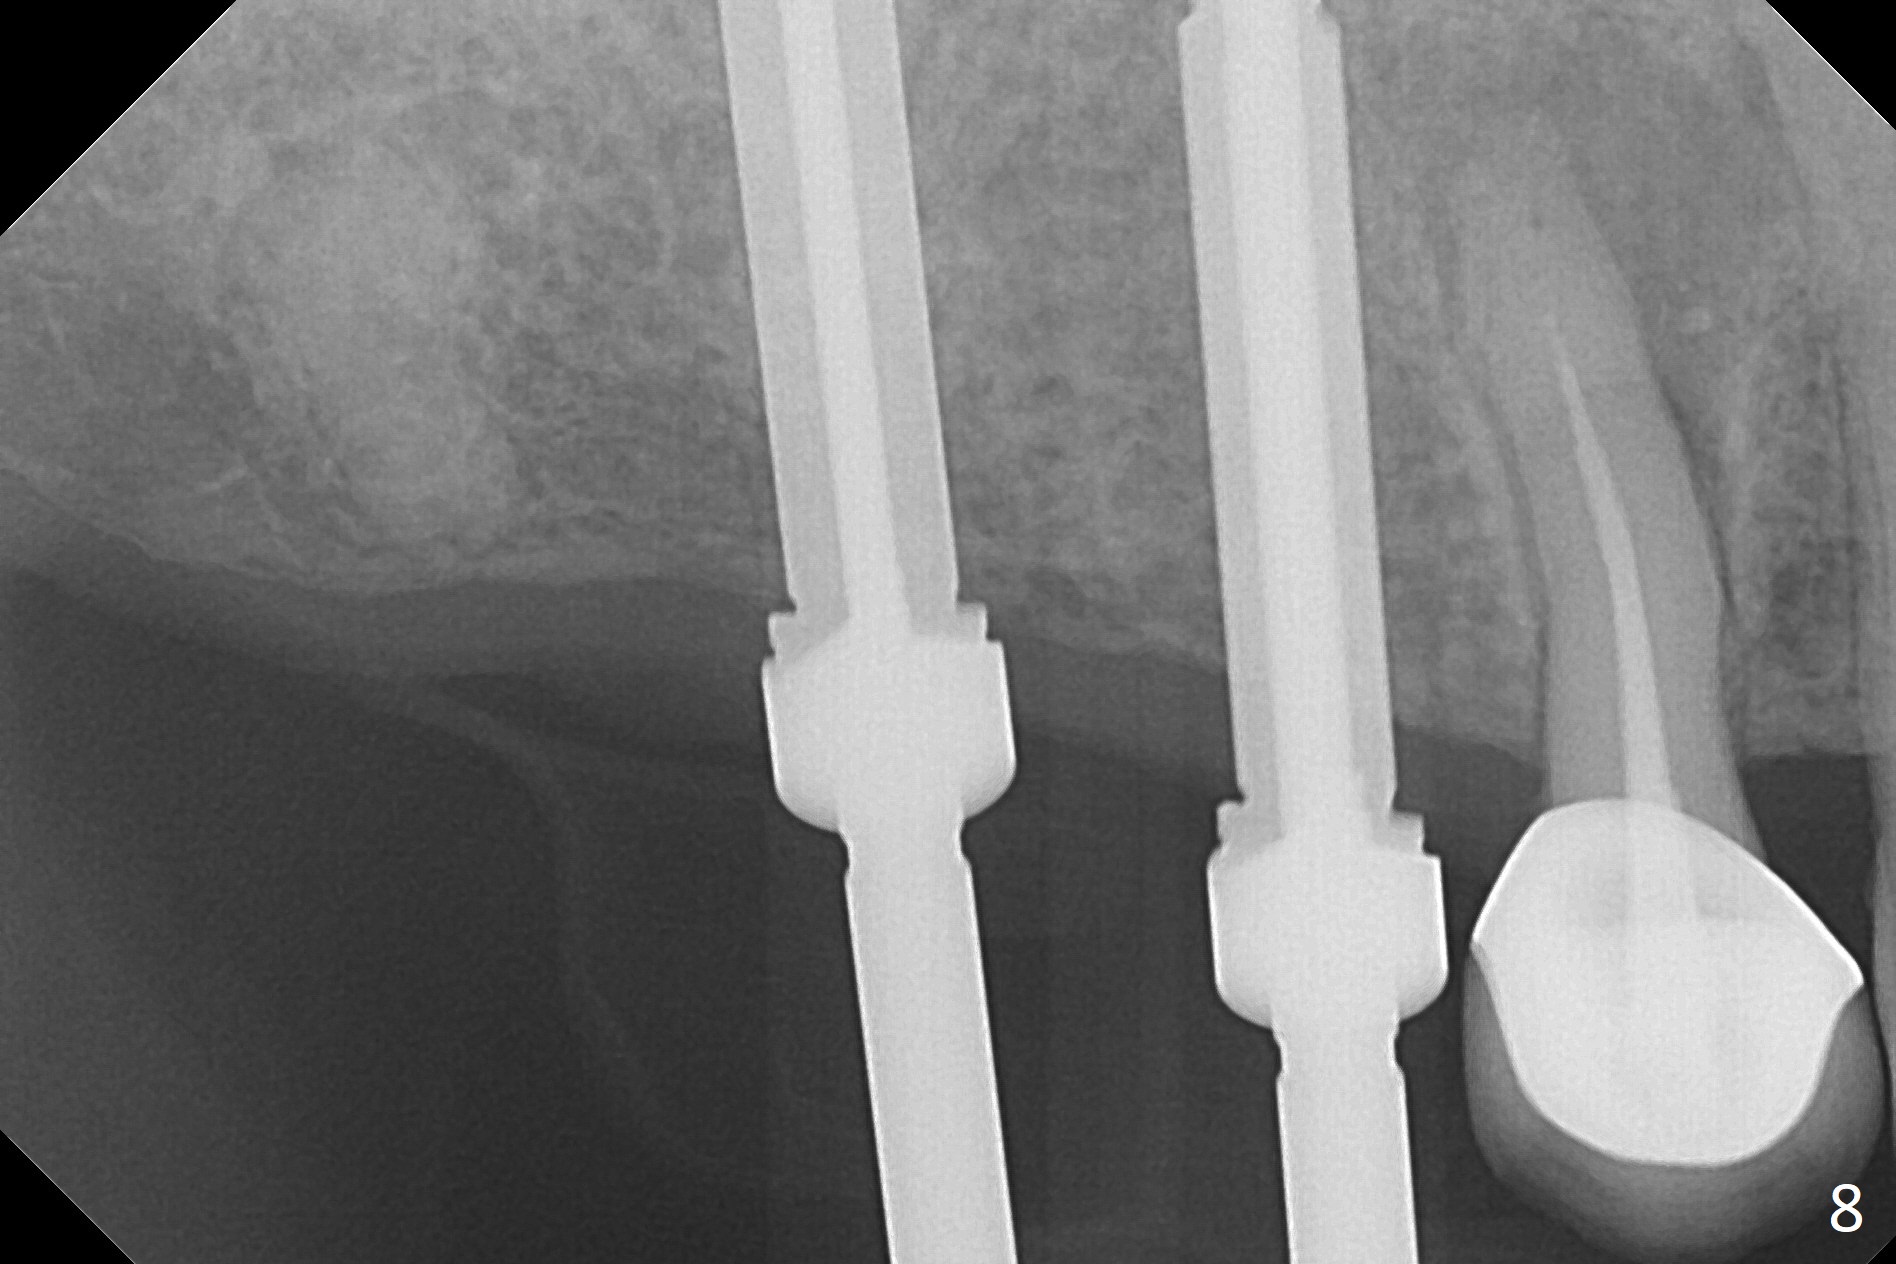

The ridge at #3,4 is wide (Fig.1). A surgical stent is placed (Fig.2) for initial osteotomy (Fig.3). When the stent is removed, the osteotomies need to move palatal (Fig.4 arrows). As two of 1.2 mm drills are in place (Fig.5), mesiodistal trajectories are found off (Fig.6). After the trajectories are corrected (Fig.7), the depth cannot be determined with PA (Fig.8, as compared to Pan (Fig.9)). Following 4.3 and 3.2 mm final drills at #3 and 4, 4.5x13 and 3.8x15 mm implants are placed with insertion torque of 35 and 50 Ncm, followed by 5.5x4(3) and 4.5x4(2) mm abutments (Fig.10). BWs show incomplete placement of the implant at #4 distal (Fig.11,12). Later the implant is placed ~ .5 mm deeper. Periodontal dressing is applied postop. CT-assisted surgical guide must be more efficient for this case with wide ridge. There is no bone loss around the implants 3 moths postop